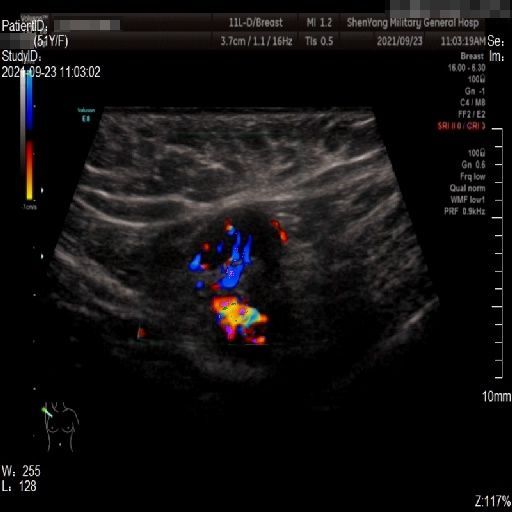

Images with certain annotations are considered noisy images in the context of the noise removal task, and corresponding images without these annotations are considered clean. Some typical images with various annotation are provided in Fig. 1.

(a)

(b)

(c)

Figure 1: Images with various annotations. (a) body marker annotation, (b) radical line annotation, (c) vascular flow annotation.